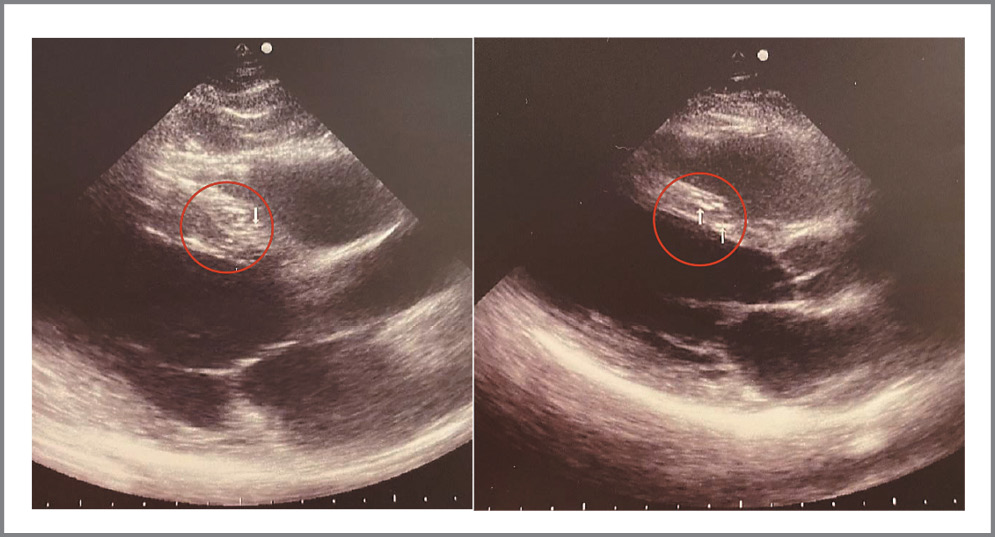

Изменения в миокарде представлены в виде округлых гиперэхогенных, единичных или немногочисленных диффузно расположенных включений от 1,5 до 3,2 мм в диаметре, локализующихся в основном в межжелудочковой перегородке или в толще задней стенки ЛЖ (рис. 4). Эти включения визуально отличались от обычно выявляемых участков мелкоочагового фиброза, например после перенесенного миокардита или при ишемической болезни сердца и кардиосклерозе, когда очаги носят преимущественно линейный характер (рис. 5). Относительно диастолической дисфункции достаточно сложно сделать однозначный вывод, так как к данному состоянию могут приводить различные факторы. Однако наличие включений в миокарде, которые гипотетически могут быть последствиями специфического миокардита или изменениями на фоне перенесенного ТМА-подобного состояния при COVID-19, и гидроперикарда соотносятся с результатами немецкой когорты пациентов [37]. Важно отметить, что обнаружение описанных изменений требует от специалиста ультразвуковой диагностики высокой квалификации и достаточного уровня насмотренности. В течение периода набора данных в поле зрения также попал пациент 21 года, не болевший COVID-19, но у которого по данным ЭхоКГ в миокарде обнаружена группа мелкоочаговых округлых гиперэхогенных включений до 2,5 мм с сохранной диастолической и систолической функцией (рис. 6).

Рис. 6. Пример включений в межжелудочковой перегородке у пациента 21 года, не переносившего COVID-19.

Fig. 6. An example of inclusions in the interventricular septum in a 21-year-old patient who didn’t have COVID-19.

Однозначное объяснение этому привести сложно, но, возможно, пациент мог перенести в анамнезе респираторную инфекцию с вовлечением миокарда, этиологическим фактором которой являлся другой представитель группы коронавирусов.